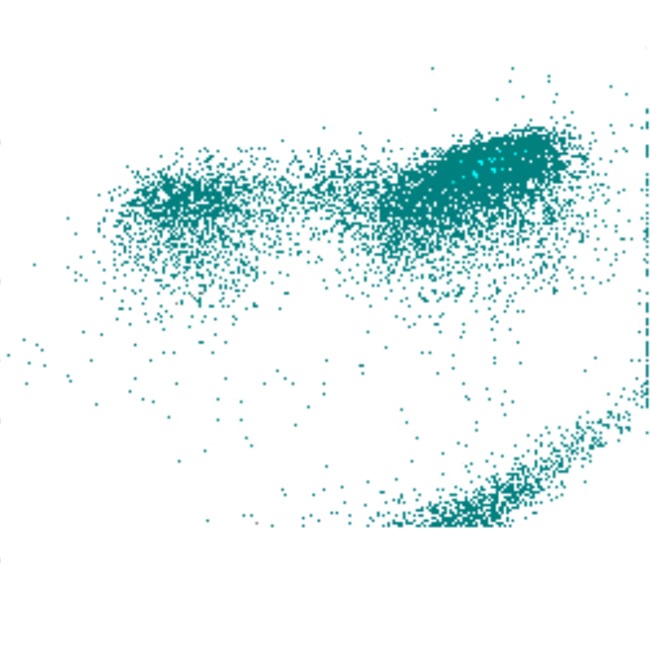

SSC scatter

SSC faible

SSC élevé